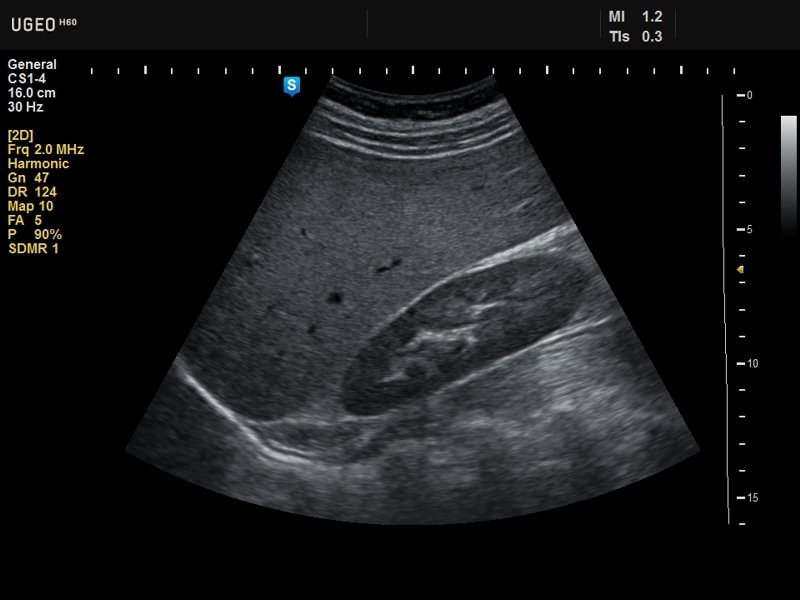

Kidney, B-mode

Kidney, B-mode (echogramm №636)

[RU] Ultrasound image №636: Kidney in B-mode.

Echogramm was received by ultrasound scanner H60 (out of production).